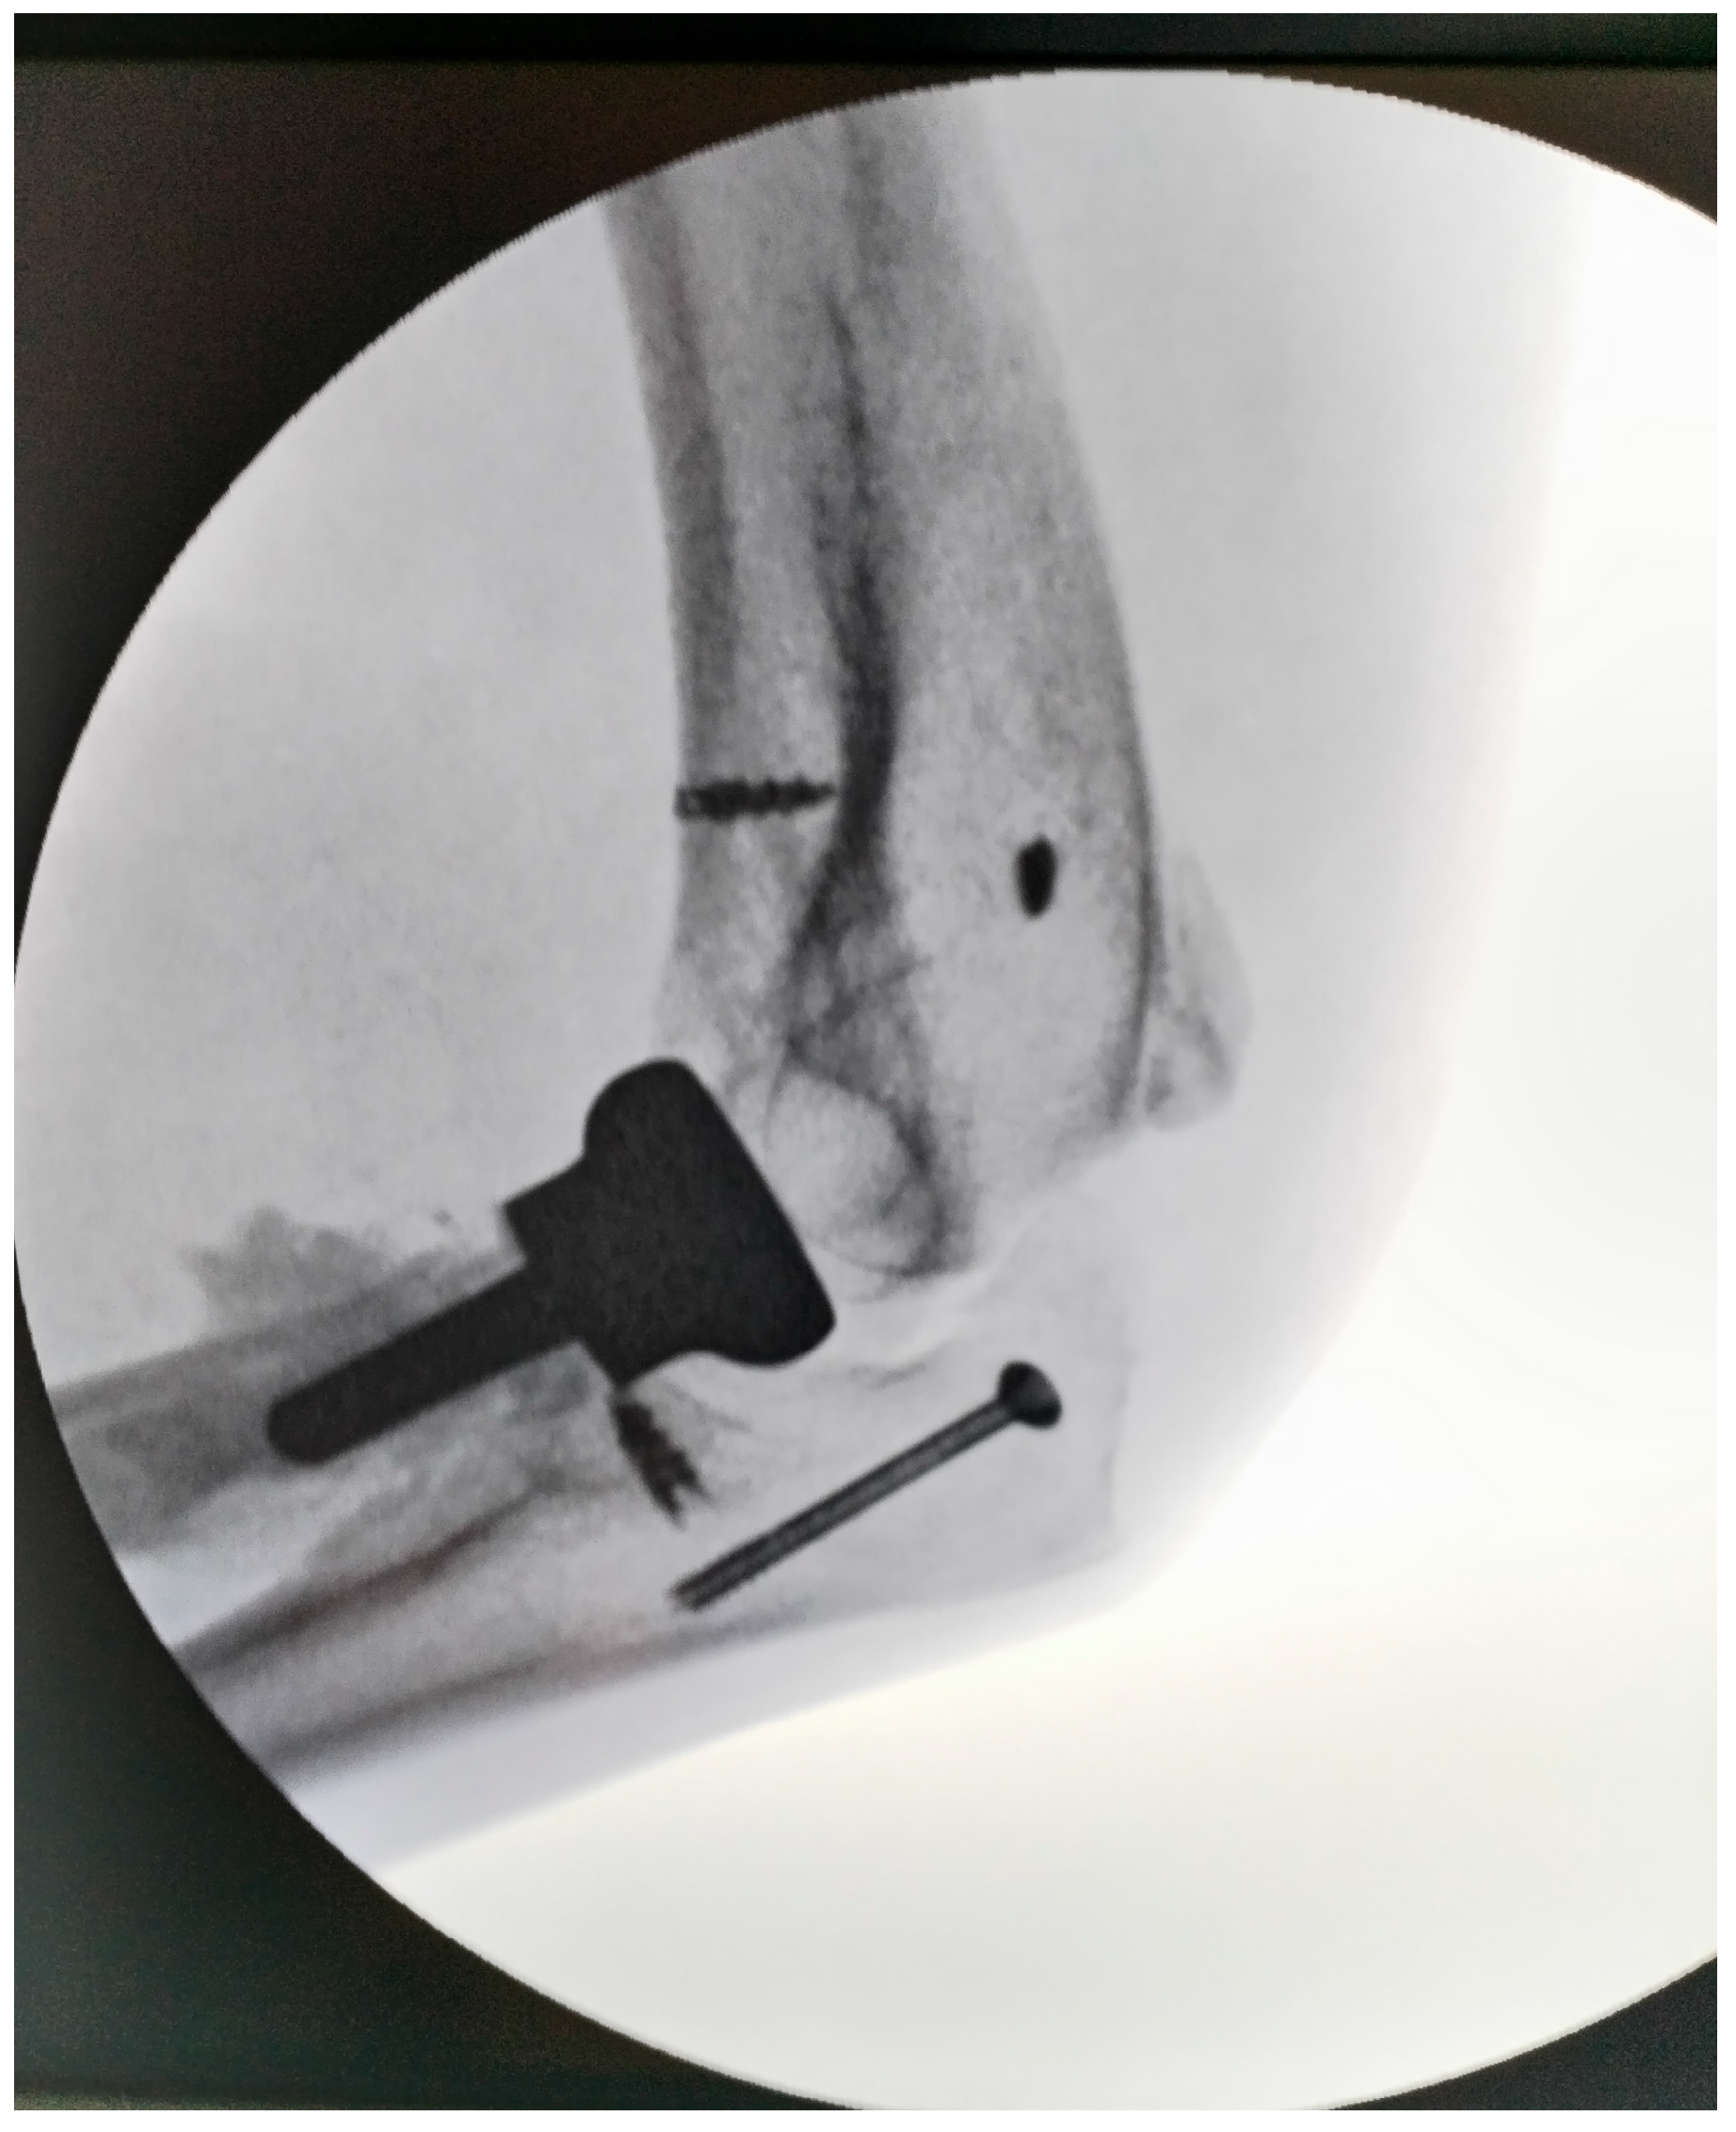

Figure 4. Intraoperative aspect of elbow (radial head arthroplasty and anchors for muscle fixation; the tip of olecranon was stabilized with a cannulated screw).

During elbow manipulation, a small olecranon fragment became displaced and was stabilized with a screw. Post-fixation, the elbow achieved a range of motion of approximately 100–120°, although full extension was limited due to contracture of the biceps and brachialis muscles. Pronation and supination were assessed with the elbow flexed at 90° and were found to be complete.

The common extensor tendons were reattached using anchors, and an anterior transposition of the ulnar nerve was performed. Soft tissues were sutured with the elbow positioned at 90° and the radius in pronation, utilizing the prosthetic radial head as a stabilizer. Postoperative radiographs were obtained to confirm proper joint alignment (Figure 4). The wound was closed in a standard fashion over a suction drain to prevent subcutaneous hematoma formation.